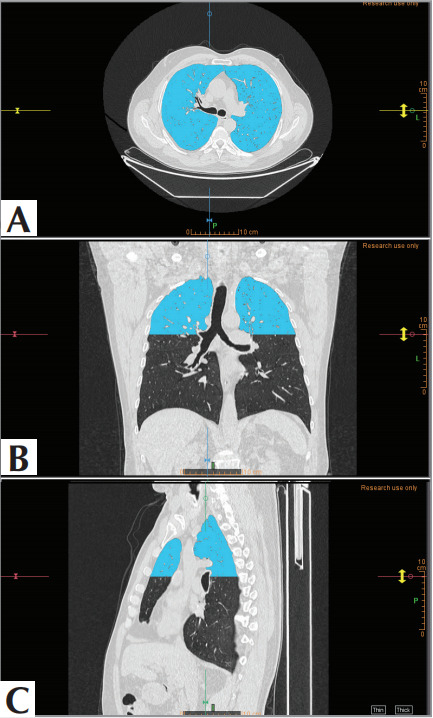

Materials and methods: Over the last 12 months, a total of 354 patients were screened based on the presence of terms such as “Fleischner”, “CLE”, and “centriacinar” in their thoracic CT reports, culminating in a study population of 82 patients. The study population was divided into Group 1 (Fleischner mild and moderate; n= 45) and Group 2 (Fleischner confluent and advanced destructive; n= 37). Volumetric segmentation was performed, focusing on the upper lobe segments of both lungs. From these segmented volumes, radiomics parameters including shape, size, first-order, and second-order features were calculated. The best model parameters were selected based on the Bayesian Information Criterion and further optimized through grid search. The final model was tested using 1000 iterations of bootstrap resampling.